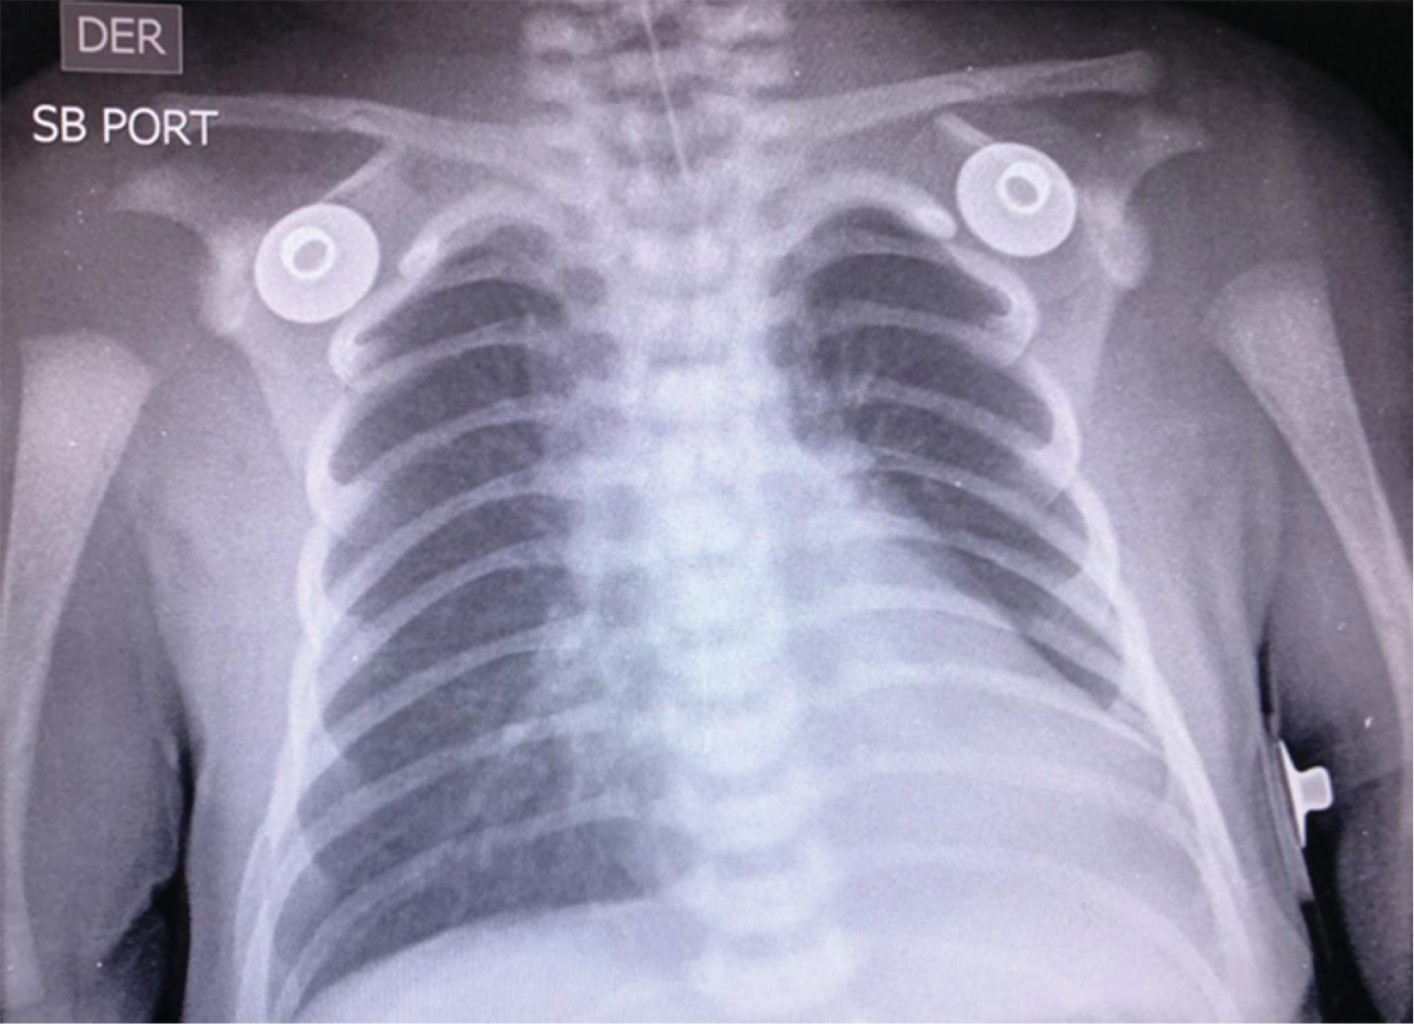

Figure 2